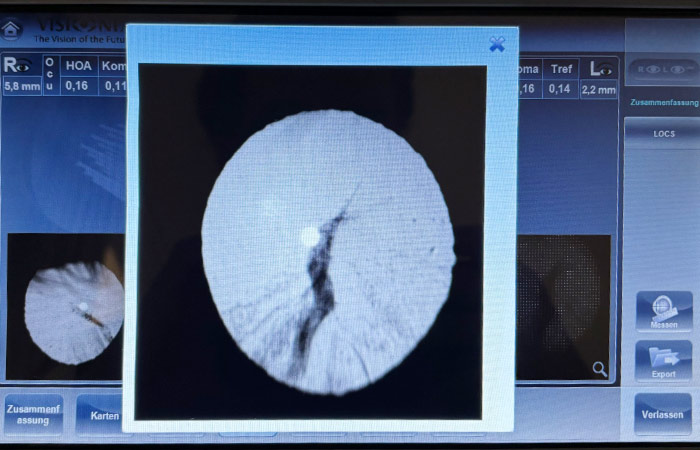

Linsentransparenzanalyse

Im Rahmen unserer Vorsorge Analyse überprüfen wir die Durchsichtigkeit Ihrer Augenlinse – ein möglicher Hinweis auf beginnende Katarakt (Grauer Star). Ergänzt durch Blendempfindlichkeitsanalyse und individuellen Sehtest entsteht ein ganzheitliches Bild Ihrer Augengesundheit.